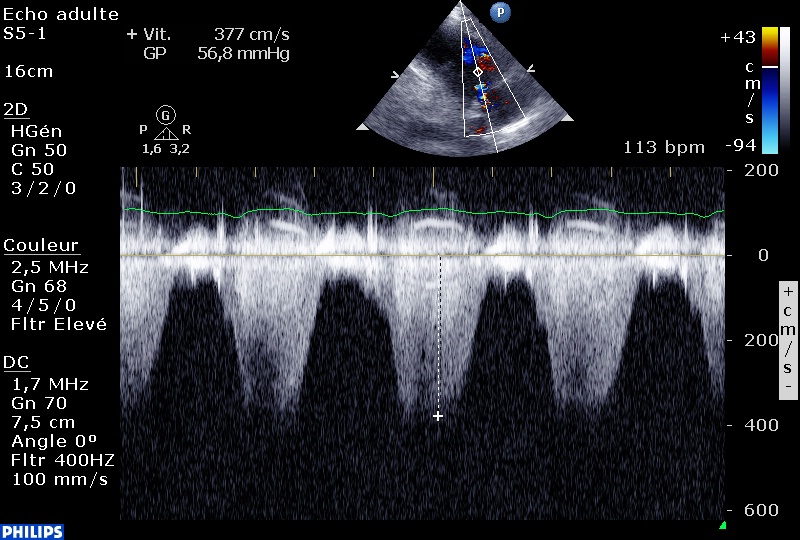

Une Vmax de le CIV à 3,6 m/sec, soit un gradient VG-VD à 55mmHg, donc une PAPs à 75 mmHg, si la pression artérielle systolique (qui est égale à la PVGs en l’absence de RAC) est à 130 mmHg.

Sur l’IT, la PAPs est calculée à 70 mmHg